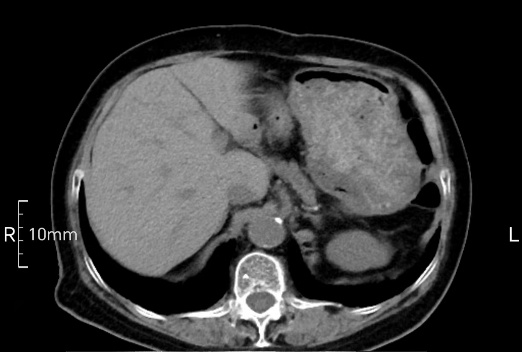

看看下面三幅便知遵醫(yī)囑的重要性。

沒禁食,胃內(nèi)全是食物,導(dǎo)致胃壁顯示不清。